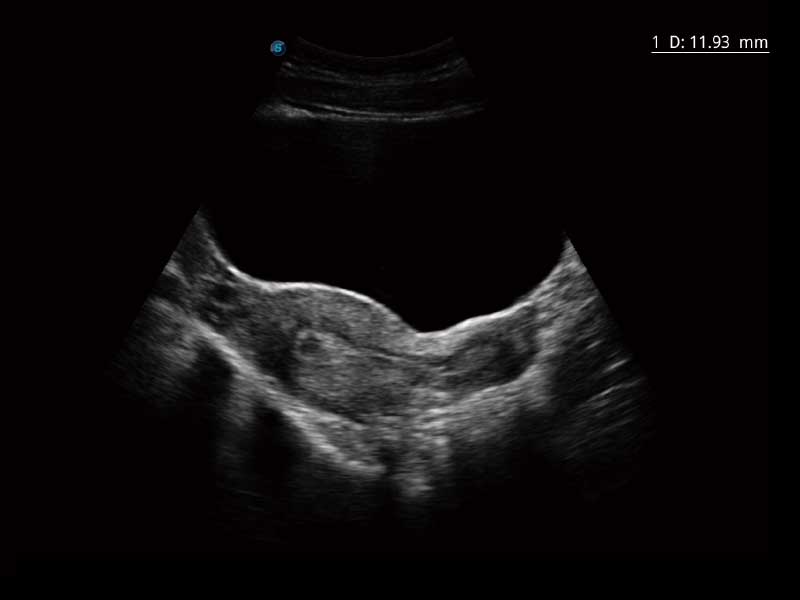

E2便携式彩色多普勒超声诊断系统采用专业的超声技术平台、高度集成化的硬件模块和结构设计、简便的操作流程、多探头接口设计,兼顾了优质图像、轻便机身以及台便两用的临床使用需求。

• 高端成像技术

μ-Scan微米成像、空间复合成像、高分辨率血流成像。

临床图